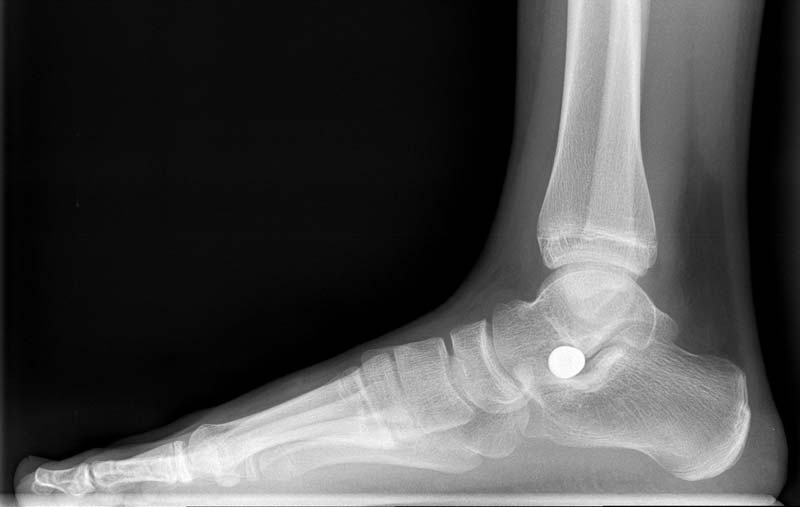

Schraube

im unteren Sprunggelenk

Nur selten sind operative Maßnahmen notwendig. Die Möglichkeiten hierbei variieren je nach Schwere der Fehlstellung. Das untere Sprunggelenk kann mit einer Schraube derart geblockt werden, dass der Fuß nicht mehr in die Fehlstellung neigt. Weitere Therapiemethoden sind Sehnenverlängerungen und knöcherne Korrekturen. Liegt eine Coalitio (siehe oben) vor, kann diese operativ gelöst werden mit und ohne knöcherne Korrektur der Fehlstellung.